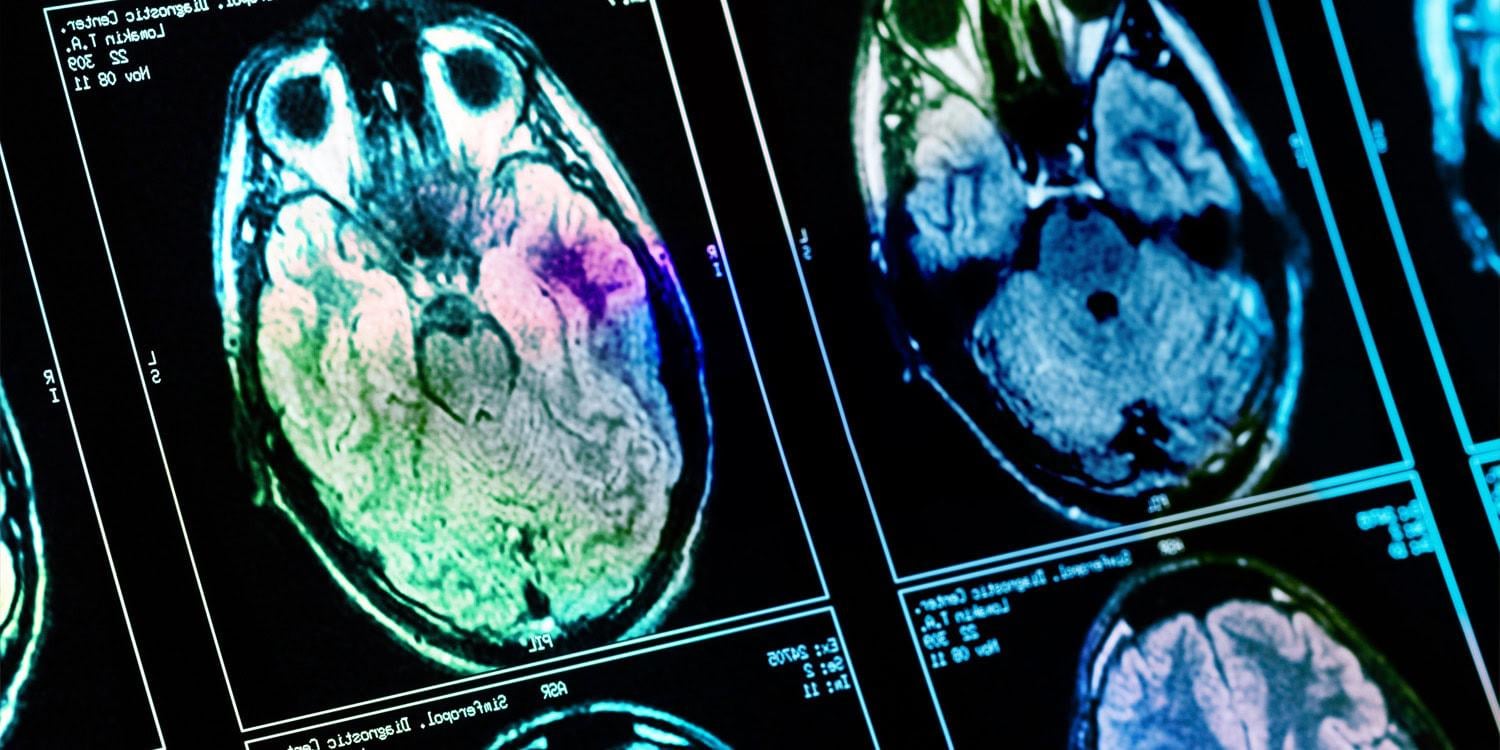

An analysis of positron emission tomography data in Korea found that **higher family income was associated with increased neural activity (estimated through increased glucose metabolism) in the caudate, putamen, anterior cingulate, hippocampus, and amygdala regions of the brain of middle-aged men**. These areas of the brain are involved in reward processing and stress regulation. The paper was published in the European Journal of Neuroscience.

Results showed that individuals with higher family income tended to have a higher education level. Higher family income was also associated with increased glucose metabolism in the caudate, putamen, anterior cingulate, hippocampus, and amygdala regions of the brain.

This means that neural activity in these regions was higher in individuals with higher family income. These regions of the brain are involved in reward processing and stress regulation. Interestingly, education level was not associated with brain activity patterns.

“Family income and education level show differential associations with brain glucose metabolism in middle-aged males. Family income is associated with elevated brain glucose metabolism in regions involved in reward processing and stress regulation, suggesting a potential link between current socioeconomic resources and neural activity. However, these findings are cross-sectional and must be interpreted as associative rather than causal. Education level does not show a significant association with brain glucose metabolism,” the study authors concluded.